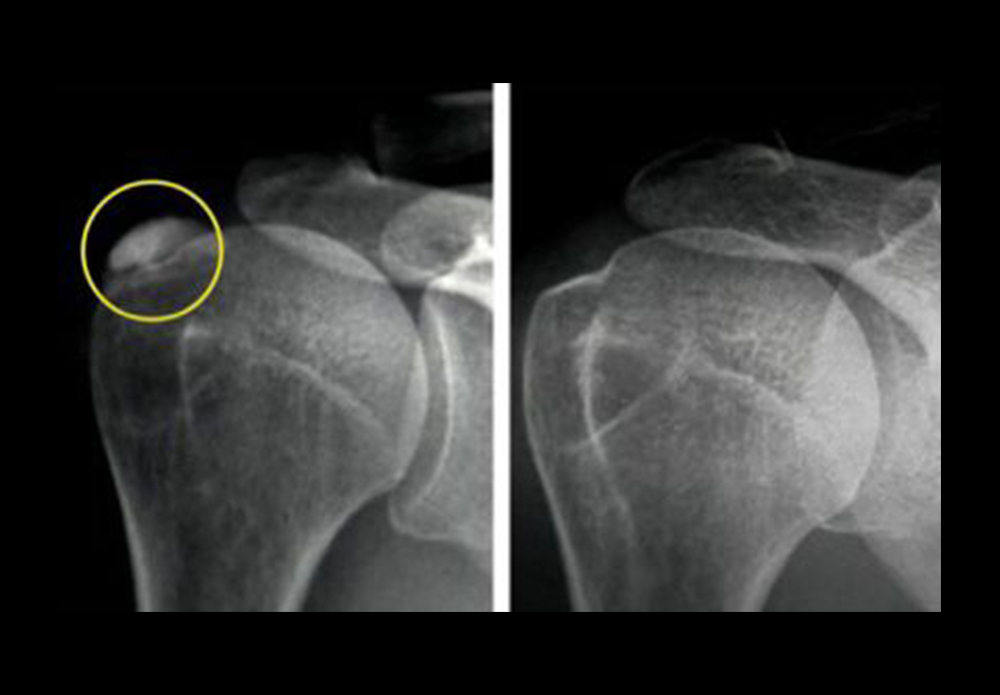

Tendinopatía calcificante de hombro